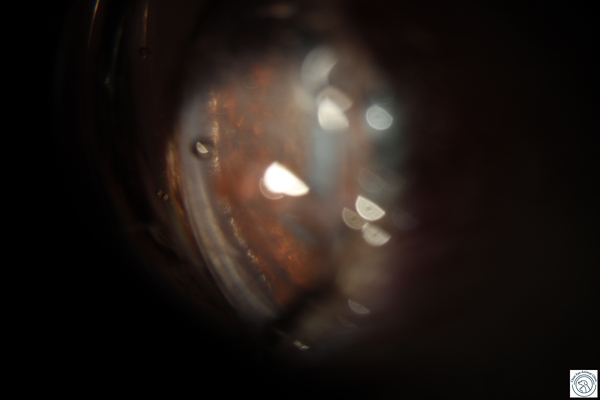

오른쪽 다리 거울과 초음파를 통해 눈 방수 배출 경로를 확인합니다.

또한 녹내장의 원인을 반드시 확인해야 합니다.수정체 탈구, 안내염, 안내종양 등의 유무 등을 확인합시다.앞에서 말한 것처럼 원인에 따라 치료 방법이 다르기 때문입니다.녹내장의 치료나 관리 녹내장은 응급 질환이므로 안압이 올라가 있다면 안압을 낮출 필요가 있습니다.